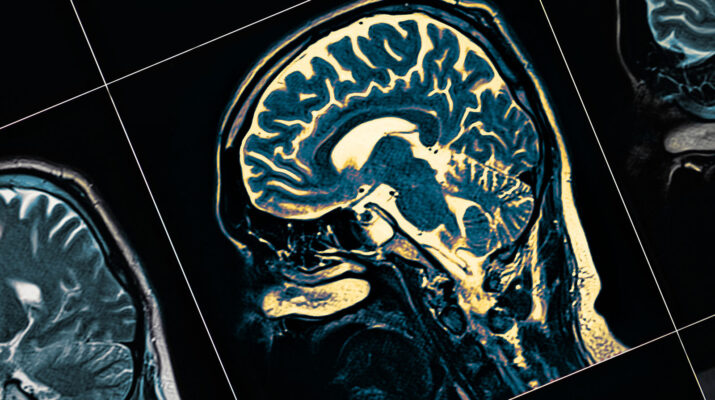

Sağlık Bilimleri Üniversitesi Gülhane Eğitim ve Araştırma Hastanesi Enfeksiyon Hastalıkları ve Klinik Mikrobiyoloji Uzmanı Doç. Dr. Savaşçı, Covid-19’un etkilerine yönelik İngiltere’de çok önemli çalışma yapıldığını belirtti. Savaşçı, “Biz kalp tutulumunu, akciğer tutulumunu, erkeklerde kısırlık yaptığını ve nörolojik etkilerini hem konuşmuştuk. Beyinde ‘gri cevher’ dediğimiz ‘hipotalamus’ dediğimiz yer önemli bir merkezi içine alan bir bölge. 45 milyonluk İngiltere’de yapılan veri tabanı taramalarında özellikle emar bulgularında Covid-19 geçiren hastaların beyinlerinde ‘gri cevher’de bir küçülme ve hücre ölümü tespit etmişler. Bu açıkçası ileride hem MS hem Alzheimer artışlarına neden olabilecek bir gelişme” dedi.